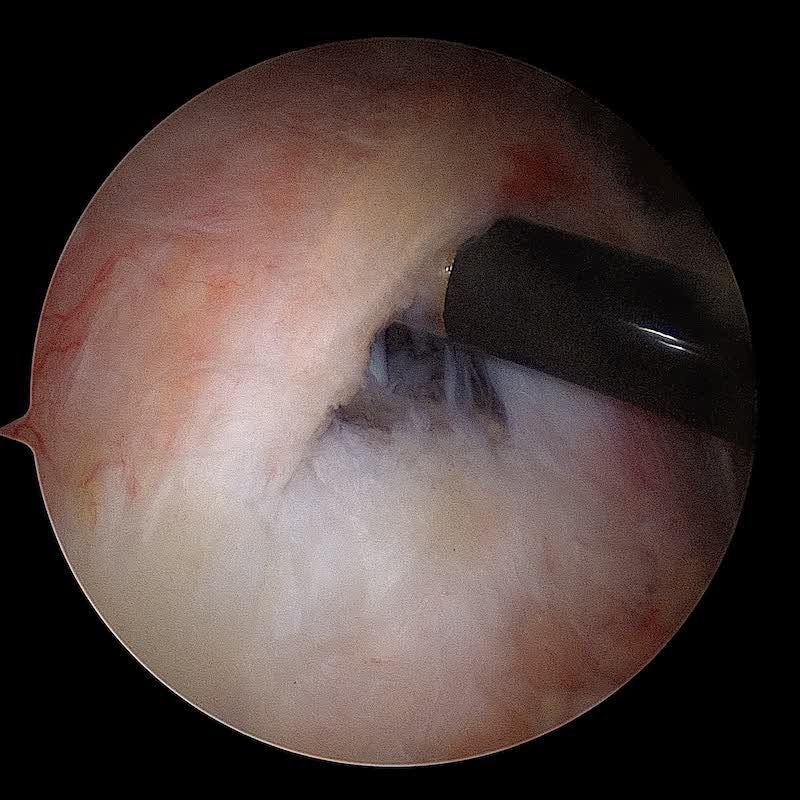

La réparation du (ou des) tendon(s) est réalisée sous arthroscopie grace à des ancres miniaturisées sur lesquelles sont fixés des fils très résistants qui permettent de réinsérer les tendons sur l'os pour permettre leur cicatrisation. Une acromioplastie et un geste sur le biceps (ténotomie ou ténodèse) sont le plus souvent associés.

Le tendon est ensuite réparée après passage des sutures au travers du tendon. Une deuxième rangée d'ancres permet de plaquer le tendon contre l'os.